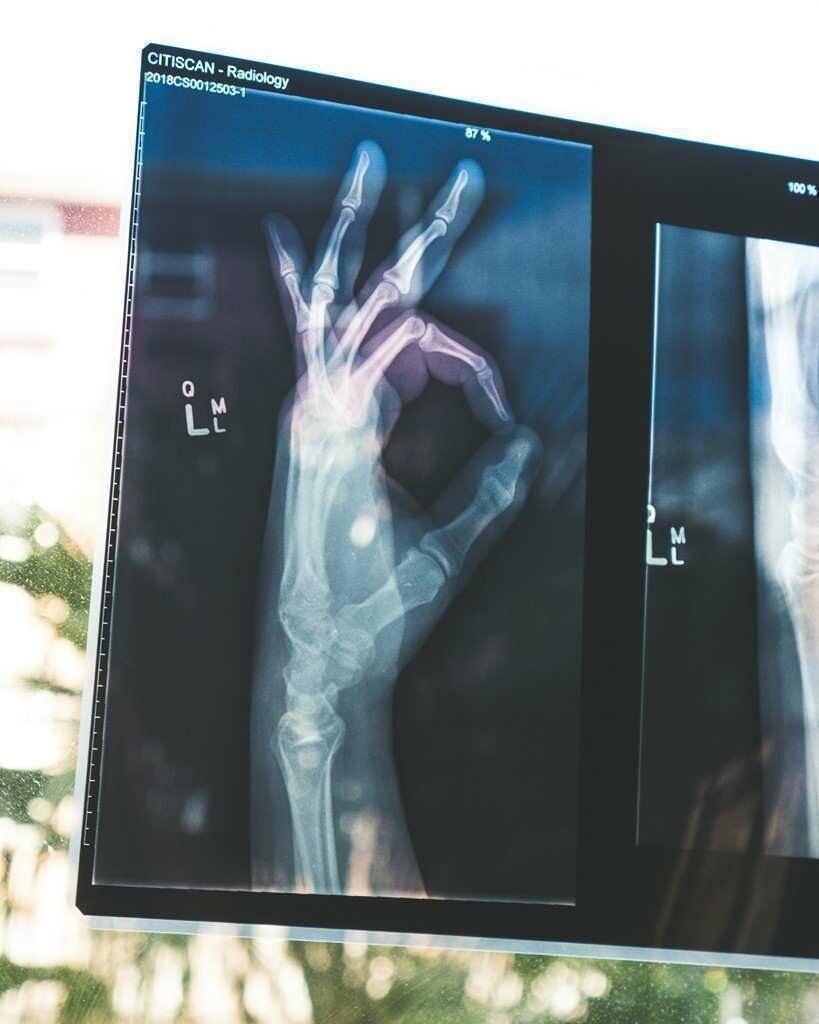

손의 신경통(neuralgia)

말초신경의 이상으로 참을 수 없는 동통과 이상감각을 호소하는 경우 이를 신경통이라고 칭한다.

신경통은 신경에의 확실한 외상에 기인될 수 있으며, 수부에서는 손목부위에서 요골신경과 정중신경의 손상시 흔히 발생된다. 그러나 신경의 손상 이외에도 타박상 등 여러 종류의 외상, 골조송증, 당뇨병이나 중금속 중독 등과 관계가 있는 각종의 신경염, 그리고 심하면 특별한 이유 가 없이 발생하는 일도 있어 이러한 질환의 존재 여부가 의심스러울 수도 있다.